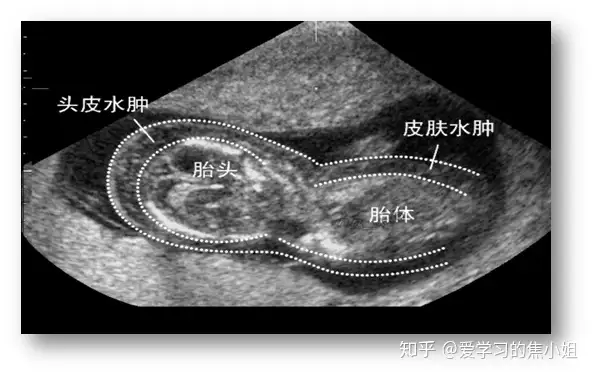

二、颈后皮肤厚度增加

测量方法:胎儿横切面,显示透明度及丘脑后,探头向后成角清晰显示小脑,在中线水平测量颅骨外侧缘及皮肤外侧缘间的距离。检查时间:16-24周。通常≥6mm视为增厚。14周之后,NT增厚通常会消退,但在部分个案中会演变成颈部水肿或颈部水囊。